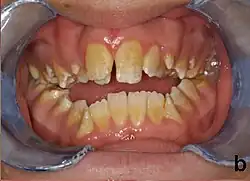

People with amelogenesis imperfecta may have teeth with abnormal color: yellow, brown or grey; this disorder can affect any number of teeth of both dentitions. Enamel hypoplasia manifests in a variety of ways depending on the type of AI an individual has (see below), with pitting and plane-form defects common.[4] The teeth have a higher risk for dental cavities and are hypersensitive to temperature changes as well as rapid attrition, excessive calculus deposition, and gingival hyperplasia.[5] The earliest known case of AI is in an extinct hominid species called Paranthropus robustus, with over a third of individuals displaying this condition.[6]

AI can be classified according to their clinical appearances:[19]

- Type 1 - Hypoplastic

- Enamel of abnormal thickness due to malfunction in enamel matrix formation. Enamel is very thin but hard & translucent, and may have random pits & grooves. Condition is of autosomal dominant, autosomal recessive, or x-linked pattern. Enamel differs in appearance from dentine radiographically as normal functional enamel.[20]

- Type 2 - Hypomaturation

- Enamel has sound thickness, with a pitted appearance. It is less hard compared to normal enamel, and are prone to rapid wear, although not as intense as Type 3 AI. Condition is of autosomal dominant, autosomal recessive, or x-linked pattern. Enamel appears to be comparable to dentine in its radiodensity on radiographs.

- Type 3 - Hypocalcified

- Enamel defect due to malfunction of enamel calcification, therefore enamel is of normal thickness but is extremely brittle, with an opaque/chalky presentation. Teeth are prone to staining and rapid wear, exposing dentine. Condition is of autosomal dominant and autosomal recessive pattern. Enamel appears less radioopaque compared to dentine on radiographs.